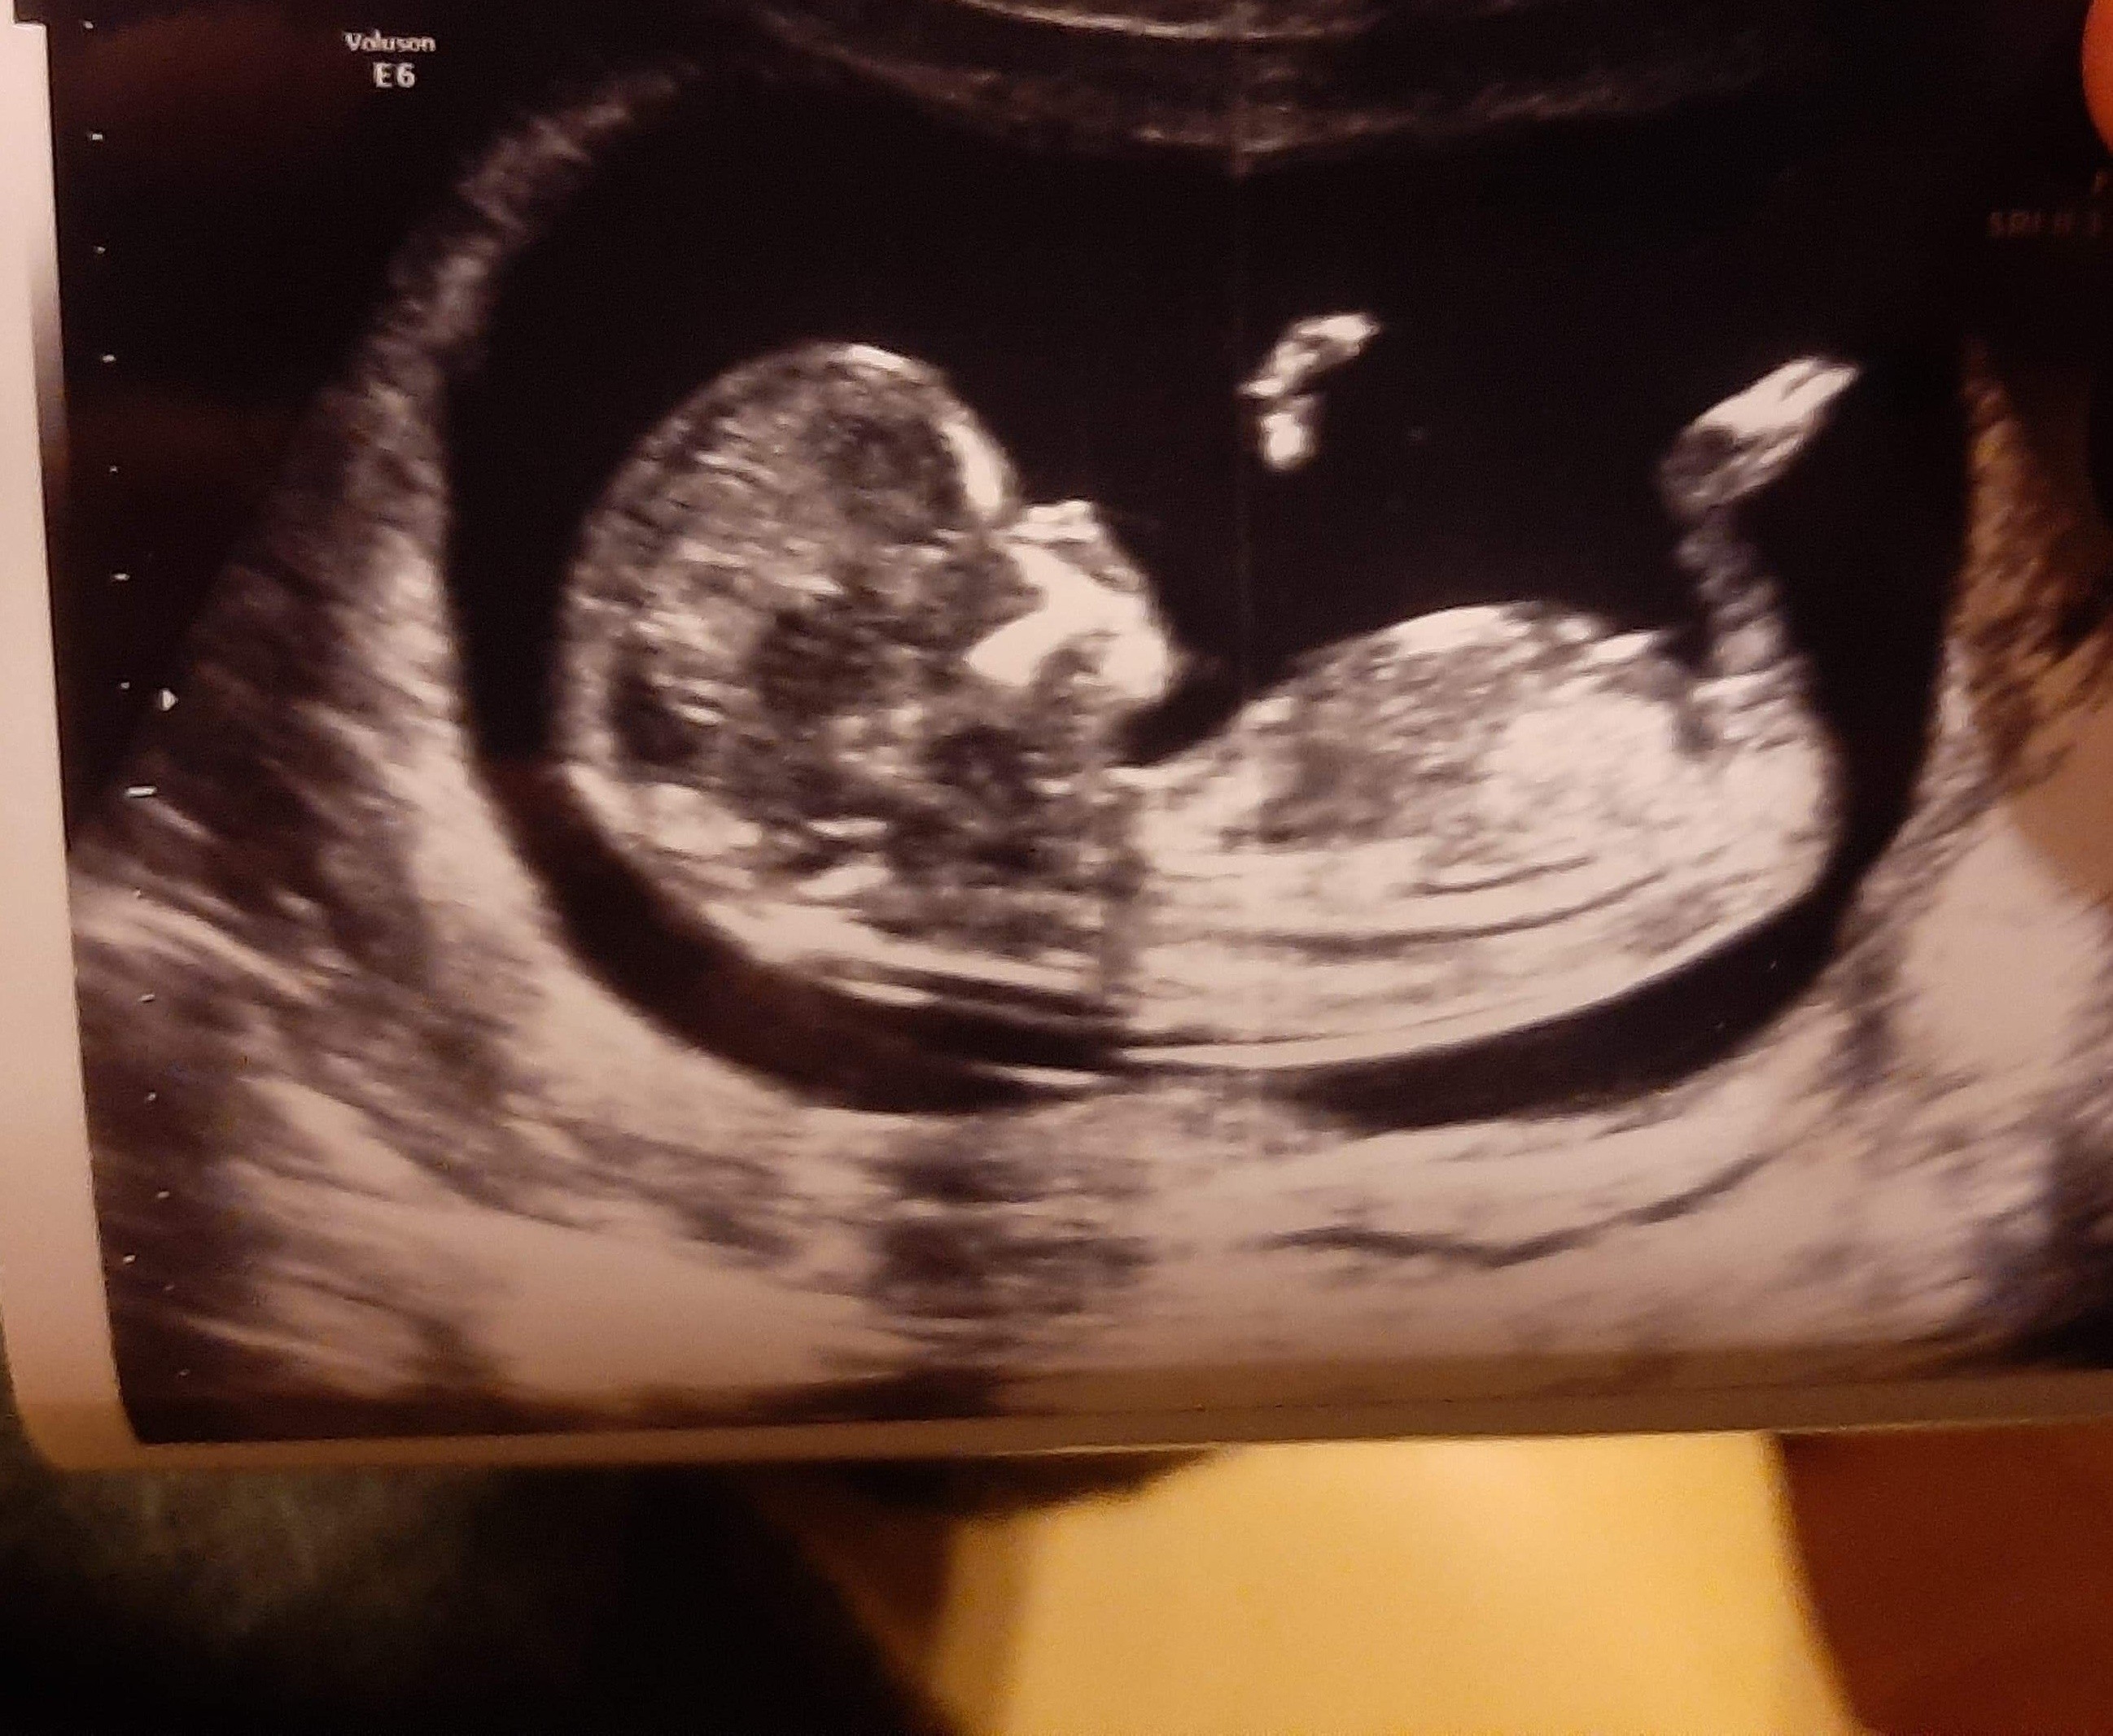

12tc. USG, chłopak czy dziewczyna?

Cześć dziewczyny, mam zdjęcia USG z 12tc+3d, podobno można stwierdzić płeć po wyrostku. Co myślicie? dziękuję za każdą odpowiedź

IMG_20191105_222148.jpg

tu jest amerykanska strona z nub theory (wyrostkiem płciowym) potiwerdzeni chłopcy Link do: Post Your Confirmed BOY Nub Theory and Potty Shots Here in Ultrasound Gender Prediction Forum

a tu potwierdzone dziewczynki

możesz sobie porównać :)